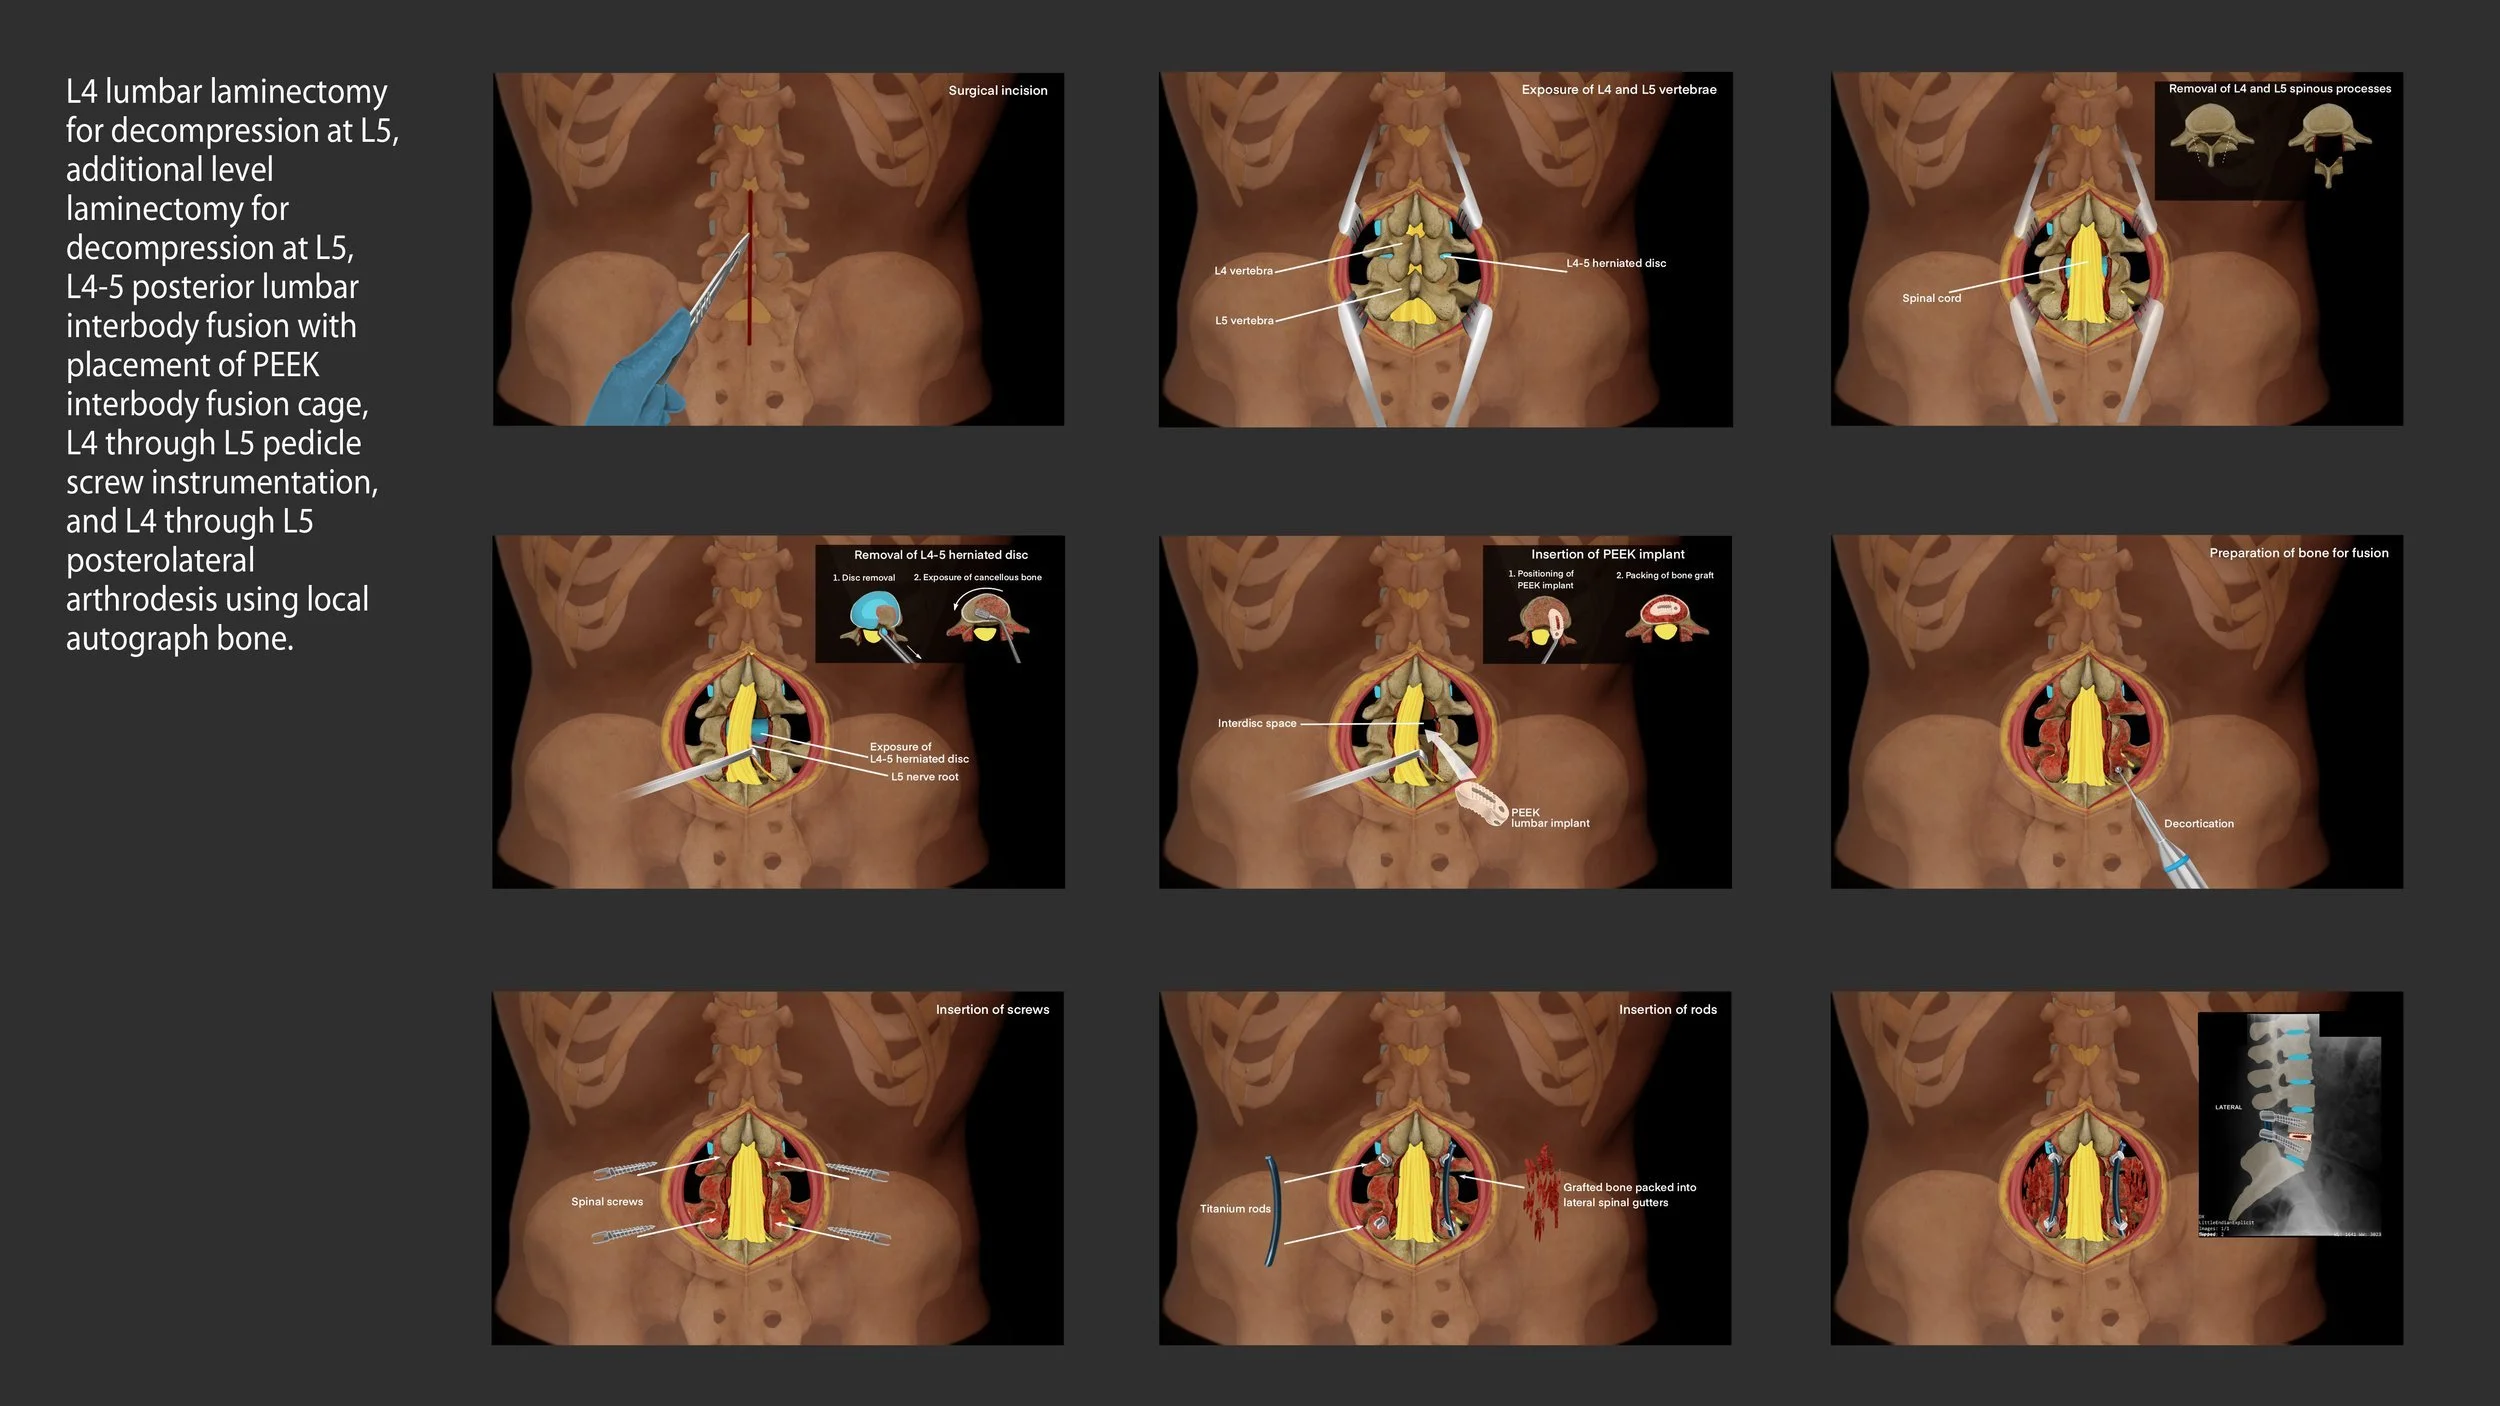

Lumbar laminectomy procedure with interbody fusion